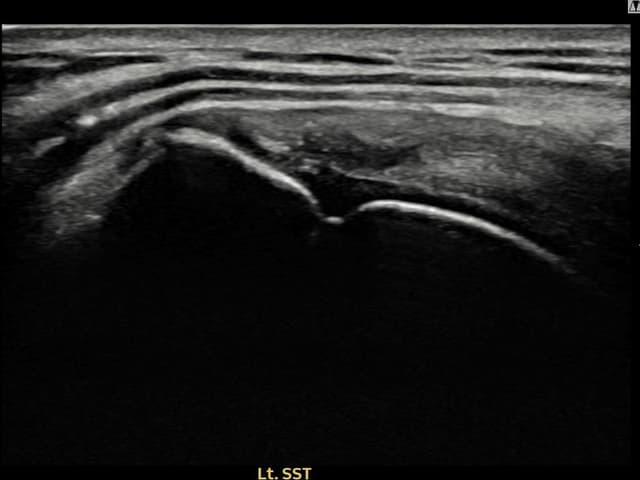

[経過期間: 24.06.04~24.08.12]

[縫縮術] 超音波検査にて左 棘上筋腱 滑液包面側部分断裂(14mm × 7mm (腱厚の約65%欠損))を確認。縫縮術施行後、腱の連続性が回復し、日常生活に復帰されました。

[経過期間: 24.06.21~24.08.30]

[縫縮術] 超音波検査にて左 棘上筋腱 関節面側部分断裂(8mm × 3mm (腱厚の約30%欠損))を確認。縫縮術施行後、腱の連続性が回復し、日常生活に復帰されました。